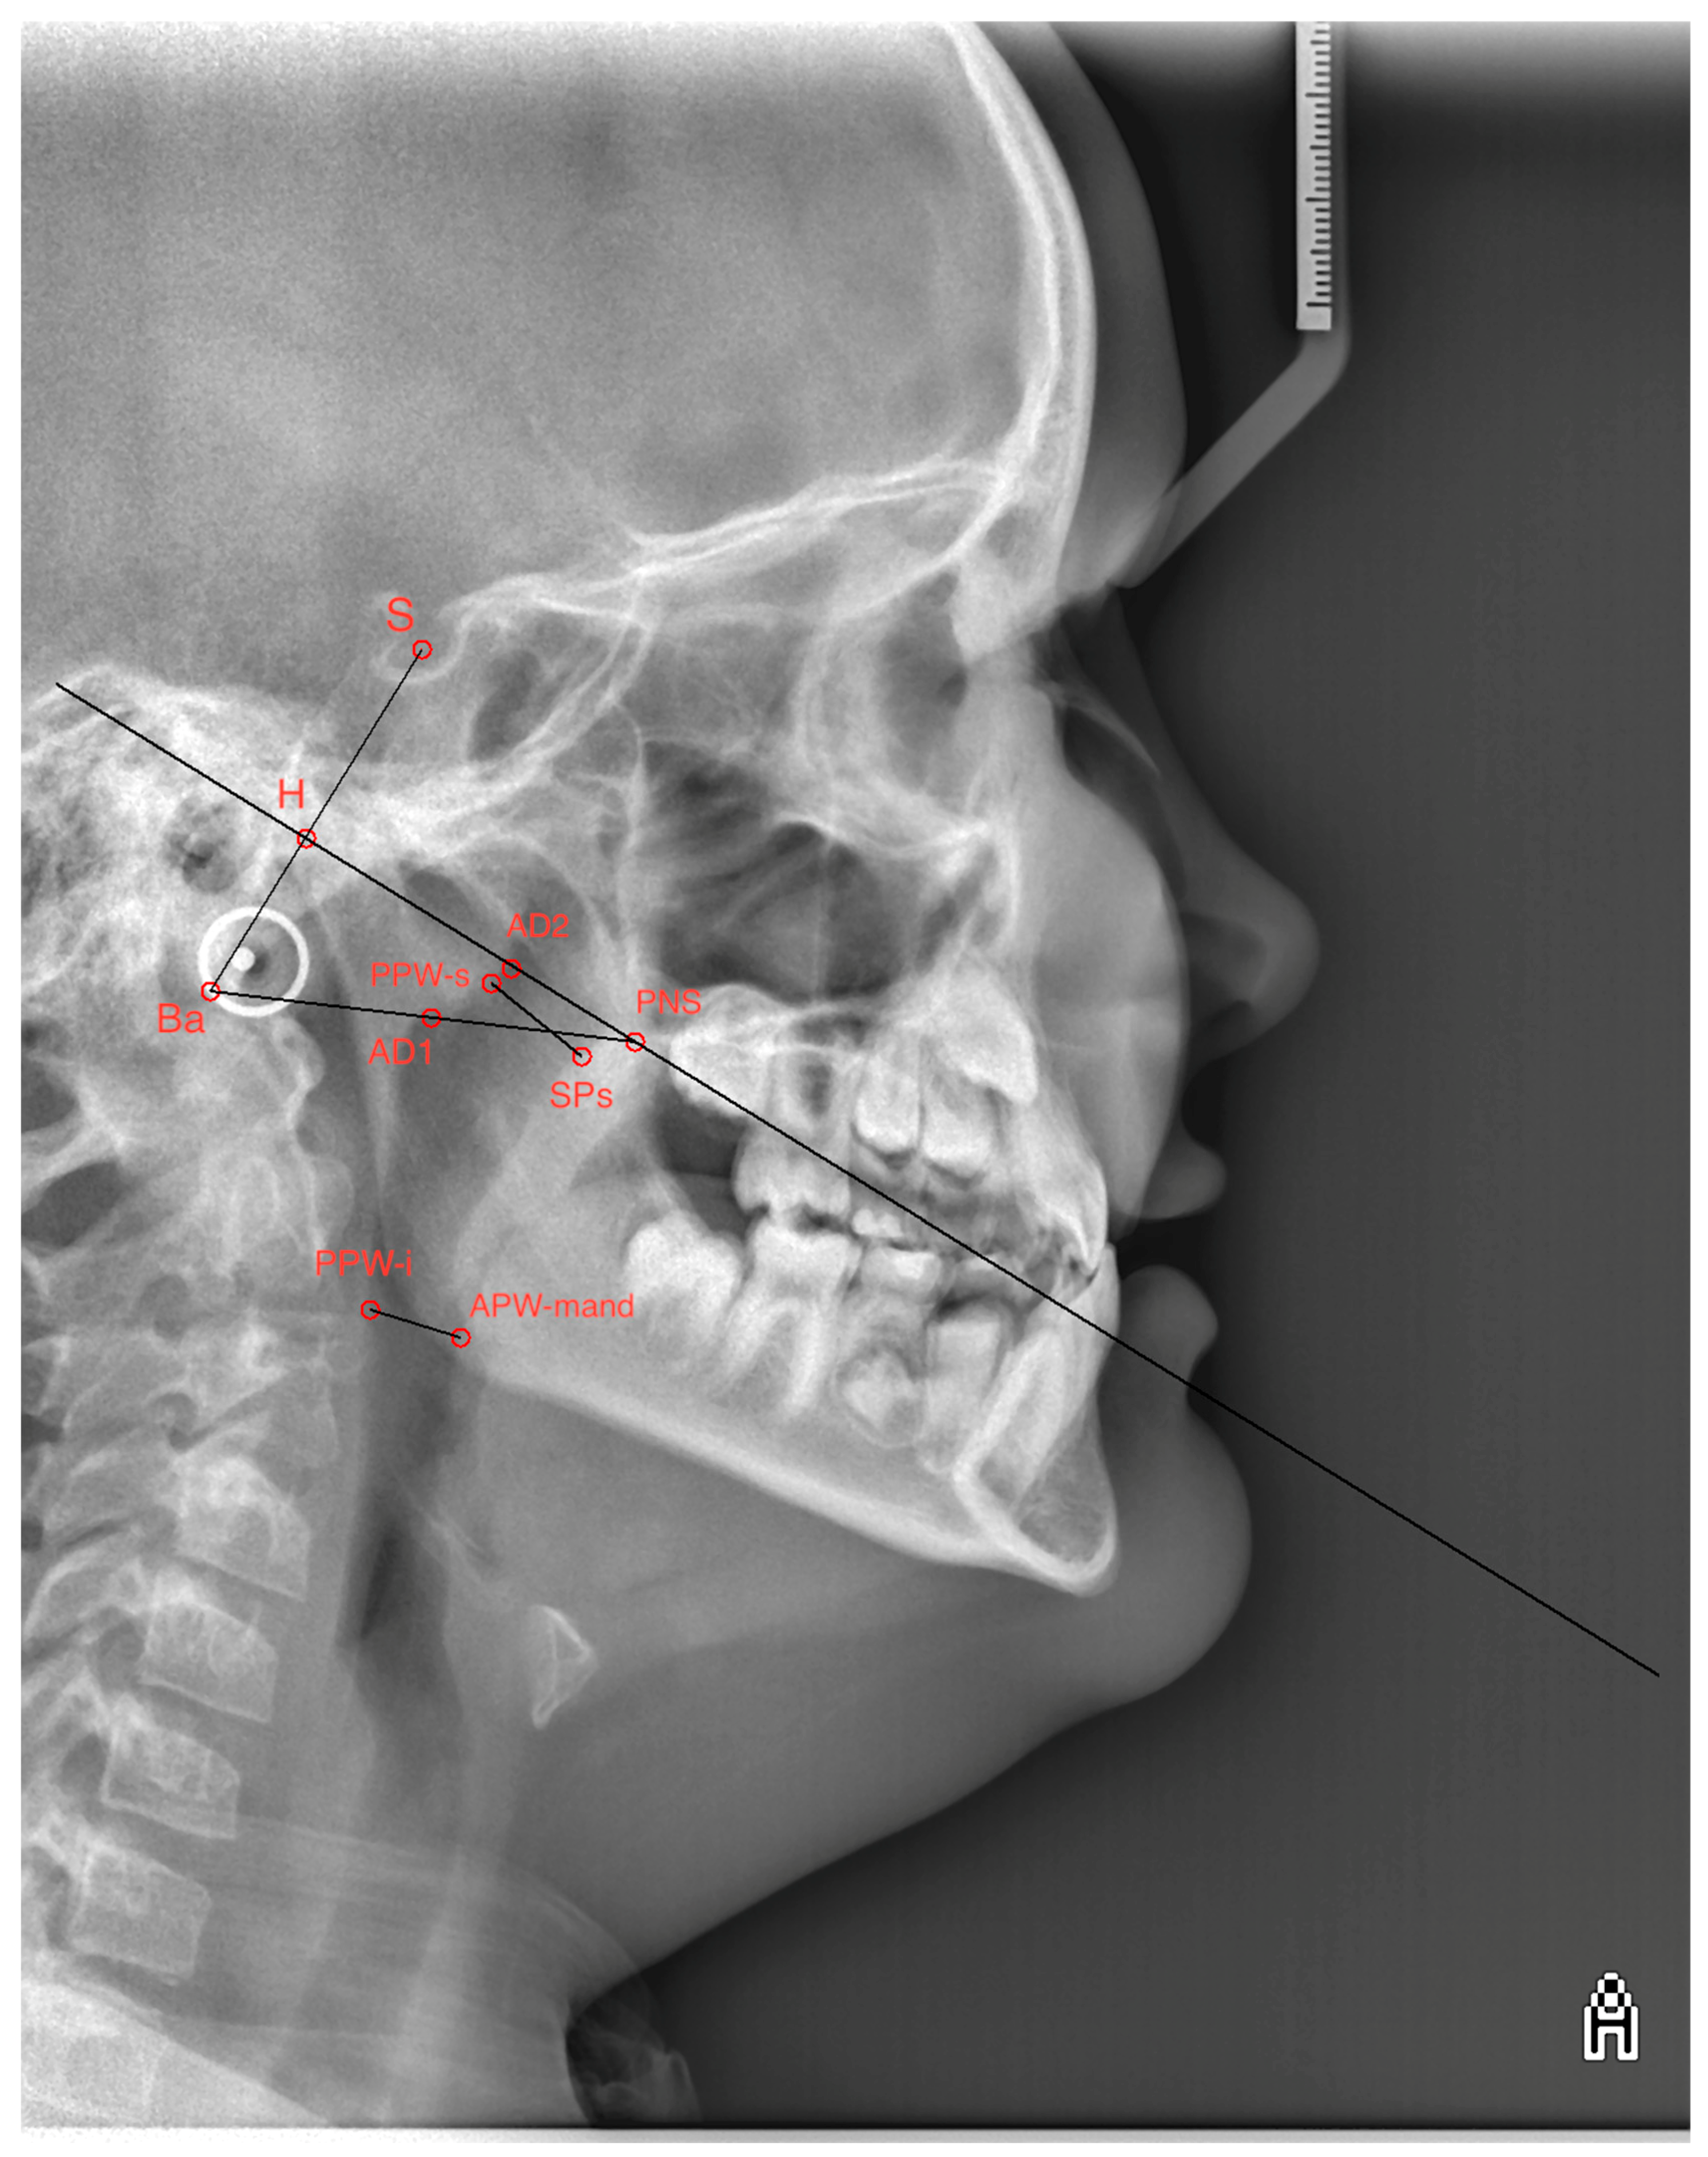

| Point, Lines and Measured Parameters | Description |

|---|---|

| S (Sella turcica) | Central point of the sella turcica |

| Ba (Basion) | Point on the lower part of the occipital bone |

| PNS (Posterior Nasal Spine) | Spina nasalis posterior |

| H (Hormion) | Point on the posterior border of the foramen magnum |

| AD2 (Adenoid upper point) | Upper point of the adenoids |

| D1 (Adenoid lower point) | Lower point of the adenoids |

| SPs (Upper soft palate dorsum) | Upper part of the soft palate dorsum |

| PPW-s (Posterior pharynx wall, superior point) | Upper point of the posterior wall of the pharynx |

| APW-mand (Anterior pharynx wall at mandible) | Anterior wall of the pharynx at the level of the mandible. |

| PPW-i (Posterior pharynx wall, inferior point) | Lower point of the posterior wall of the pharynx |

| SBa line | Line defined by the points S and Ba |

| SBa line|PNS | Line perpendicular to the SBa line passing through the PNS point |

| BaPNS line | Line defined by the points Ba and PNS |

| Upper airway | Distance between the points AD2 and PNS |

| Upper adenoid | Distance between the points H and AD2 |

| Lower airway | Distance between the points AD1 and PNS |

| Lower adenoid | Distance between the points Ba and AD1 |

| Upper pharynx | Minimal distance between the point SPs and the closest point on the posterior pharyngeal wall (PPW-s) |

| Lower pharynx | Minimal distance between the point APW-mand and the closest point on the posterior pharyngeal wall (PPW-i) |